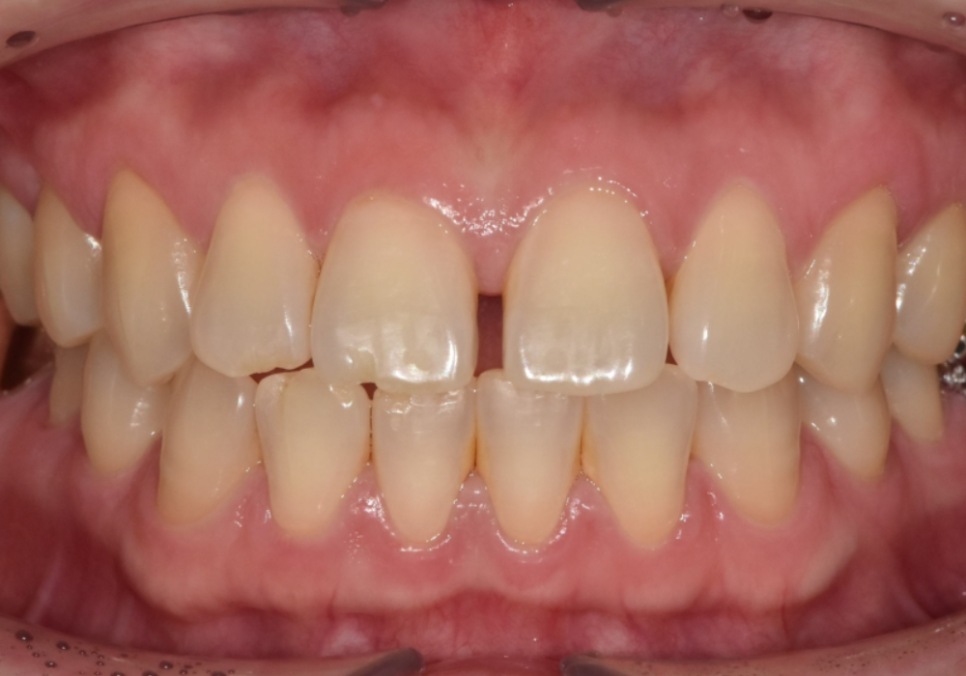

얼마 전 저희 치과를 찾으신 환자분은

가운데 앞니가 벌어진 상태였고,

동시에 왼쪽 위 어금니(#26)도

상실된 상태였어요.

라미네이트를 통해

앞니 4개의 균형을 맞추고 나니,

단 며칠 만에 인상이 훨씬 단정해지셨습니다.